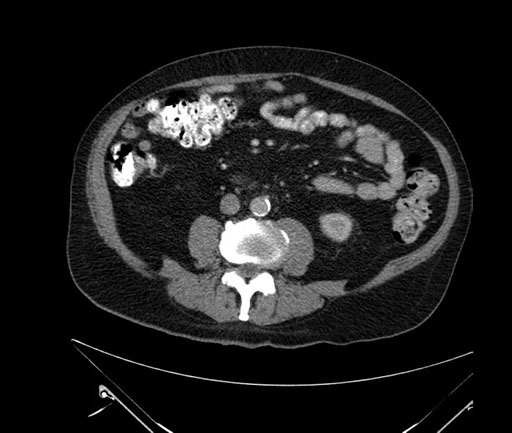

Coronal - stented